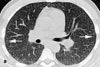

CT findings. A CT scan of the chest is obtained 2 days later for further characterization of the nodules (B). The scan demonstrates extensive miliary nodules randomly distributed throughout both lungs. The nodules are superimposed on diffuse ground-glass opacities (hazy areas of opacity that do not obscure pulmonary vessels). Septal lines are also present at the lung bases. Compared with the images of the lung bases seen on the abdominal CT scan, the nodules have rapidly progressed over 2 days.

Like chest radiographs, CT scans of patients with pulmonary talc granulomatosis usually reveal a diffuse pattern of micronodules. As in the case presented here, the CT scan may show additional findings, such as ground-glass opacity and septal lines. Additional CT findings may include conglomerate masses (with the occasional presence of high-attenuation foci) and lower lobe-predominant panacinar emphysema.2 Several investigators have reported a progression of talc disease on serial imaging studies similar to the progression found in silicosis, with a diffuse fine nodular pattern progressing to upper lobe, high-attenuation conglomerate masses.2-5